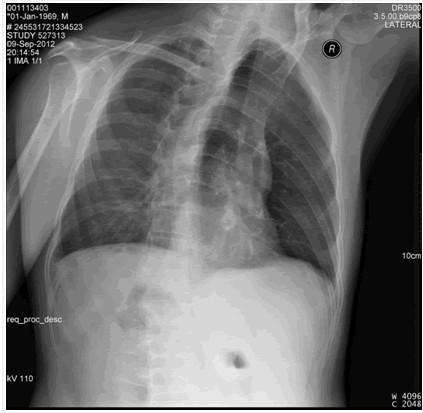

后肋骨折

图示为右侧3,5,6,7,8后肋骨折。